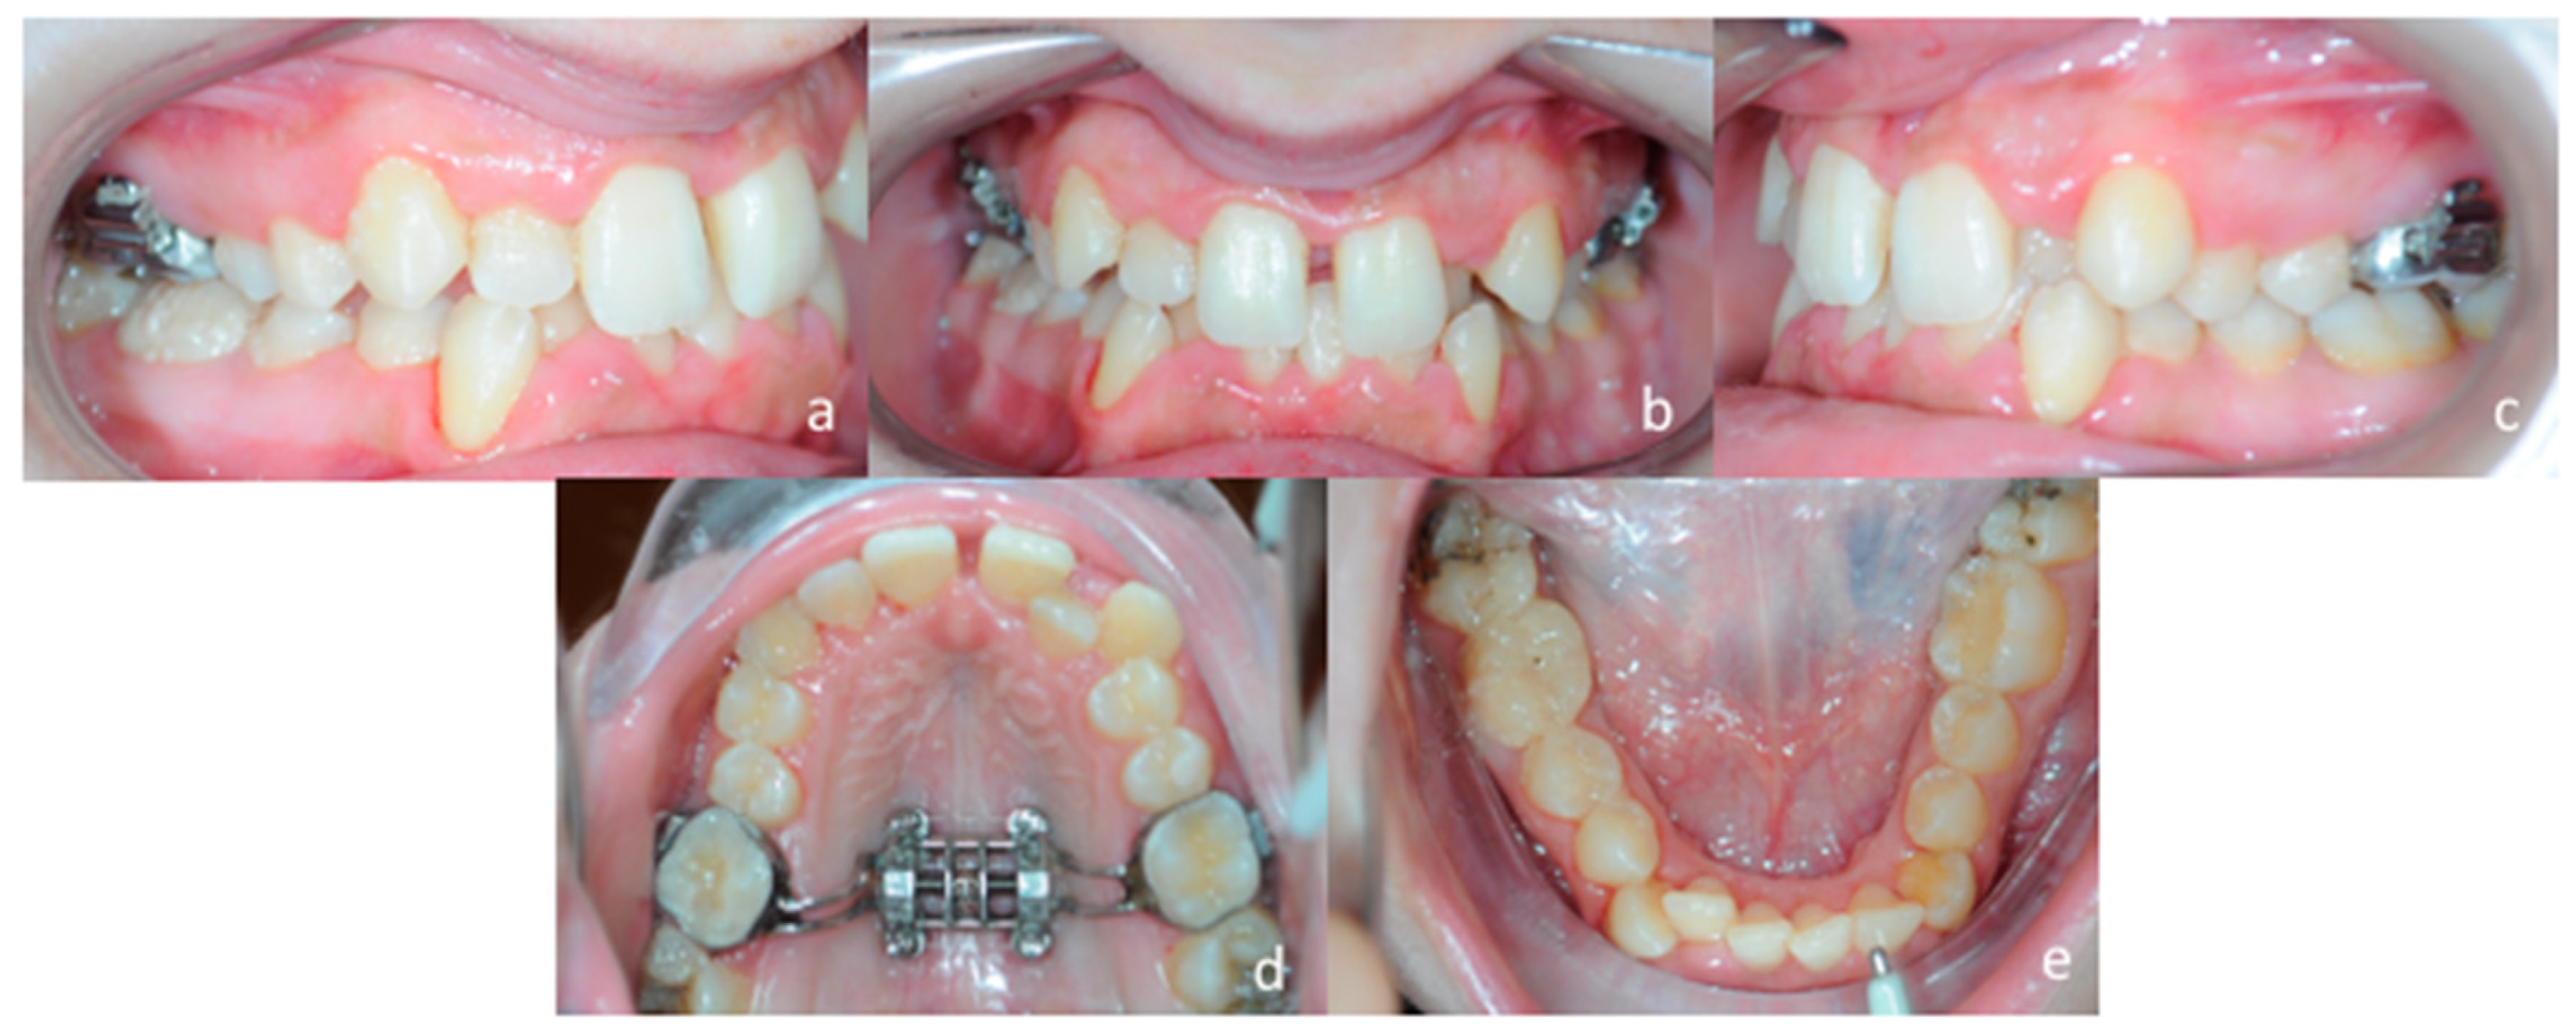

3.1. Diagnosis and Treatment Plan

3.2. Digital Workflow for Planning MSE Device